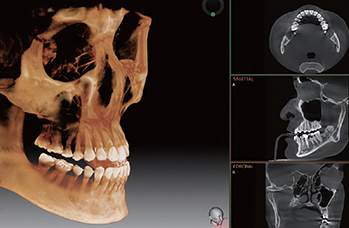

정확성 높은 식립의 노하우

3D 디지털 진단을 통한 체계적인 계획

전체 임플란트는 위턱과 아래턱의 교합, 잇몸뼈의 상태 및

얼굴 변화 등 모든 것을 고려해 식립해야 합니다.

서울더자연치과는 3D 디지털 기술의 정밀 진단을 바탕으로

수술 계획을 세워 수술을 집도합니다.

치료기간 : 2021.04.12~2021.09.15